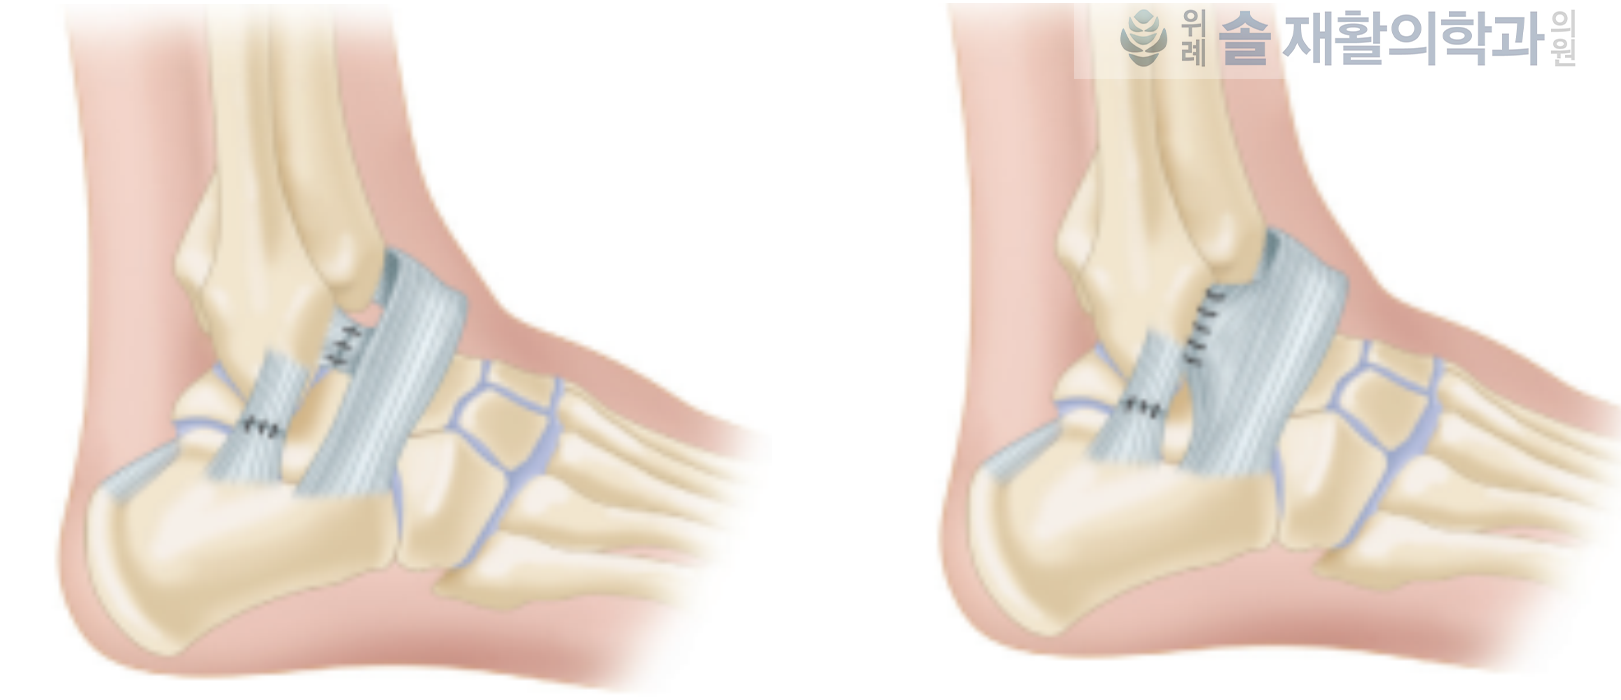

발목 인대 파열로 수술하는 경우는?

'만성 불안정성'이 존재하는 경우에는 수술을 고려하게 됩니다. 발목관절의 만성 불안정성은 손상 후 6개월이 지났음에도 뛰거나 걸을 때 발목의 흔들거림이 느껴지거나, 진찰상 명확한 불안정성이 지속되는 경우를 말하게 됩니다. 이러한 경우는 더 이상 회복될 가능성이 보이지 않고, 재손상의 가능성이 높기 때문에 인대 접합술을 시행하게 됩니다.